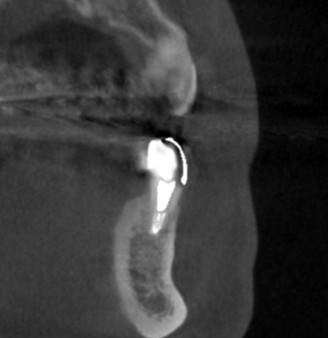

下の写真が、手術前後のCTです。